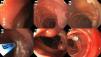

Ingresa al servicio de urgencias con melena profusa con anemia severa microcítica-hipocrómica con una hemoglobina de 3.5g/dl; pruebas de función hepática normales y anticuerpos anti-transglutaminasa negativos. La paciente rechazó uso de hemoderivados, por lo que fue manejada con hierro intravenoso (1,000mg de carboximaltosa férrica) más epoetina alfa subcutánea (4,000UI/día durante 10 días). El origen del sangrado no fue explicado por la esofagogastroduodenoscopia (EGD) y colonoscopia inicial. En nuestro centro se repitieron las endoscopias, que revelaron una trama vascular submucosa prominente en duodeno, íleon terminal y colon, sin sangrado activo (Fig. 1A, 1B, 1C, 1D, 1E). La angiografía por tomografía computada (TC) era normal. La videocápsula endoscópica (VCE) reveló múltiples angiodisplasias y flebectasias del intestino delgado (Fig. 1F). La enteroscopía profunda anterógrada con monobalón mostró en el yeyuno distal angiodisplasias y flebectasias con puntos rojos, tratadas con argón plasma (APC) (Fig. 2A, 2B, 2C, 2D). Se instalaron clips endoscópicos en uno de los vasos dilatados debido a sangrado (Fig. 2E, 2F). Evolucionó favorablemente sin nuevos episodios de sangrado, con una hemoglobina 8.5mg/dl al alta y 13.5mg/dl a los tres meses de seguimiento.

Imágenes de esofagogastroduodenoscopía, colonoscopia y video cápsula endoscópica (VCE) mostrando anormalidades vasculares. (A) Trama vascular submucosa prominente en el bulbo duodenal. (B) Flebectasia en la segunda porción del duodeno. (C) Trama vascular submucosa prominente en el íleon terminal. (D) Flebectasia en el colon transverso. (E) Trama vascular submucosa prominente en colon. (F) Imagen de VCE que muestra una pequeña angiodisplasia sin hemorragia activa.